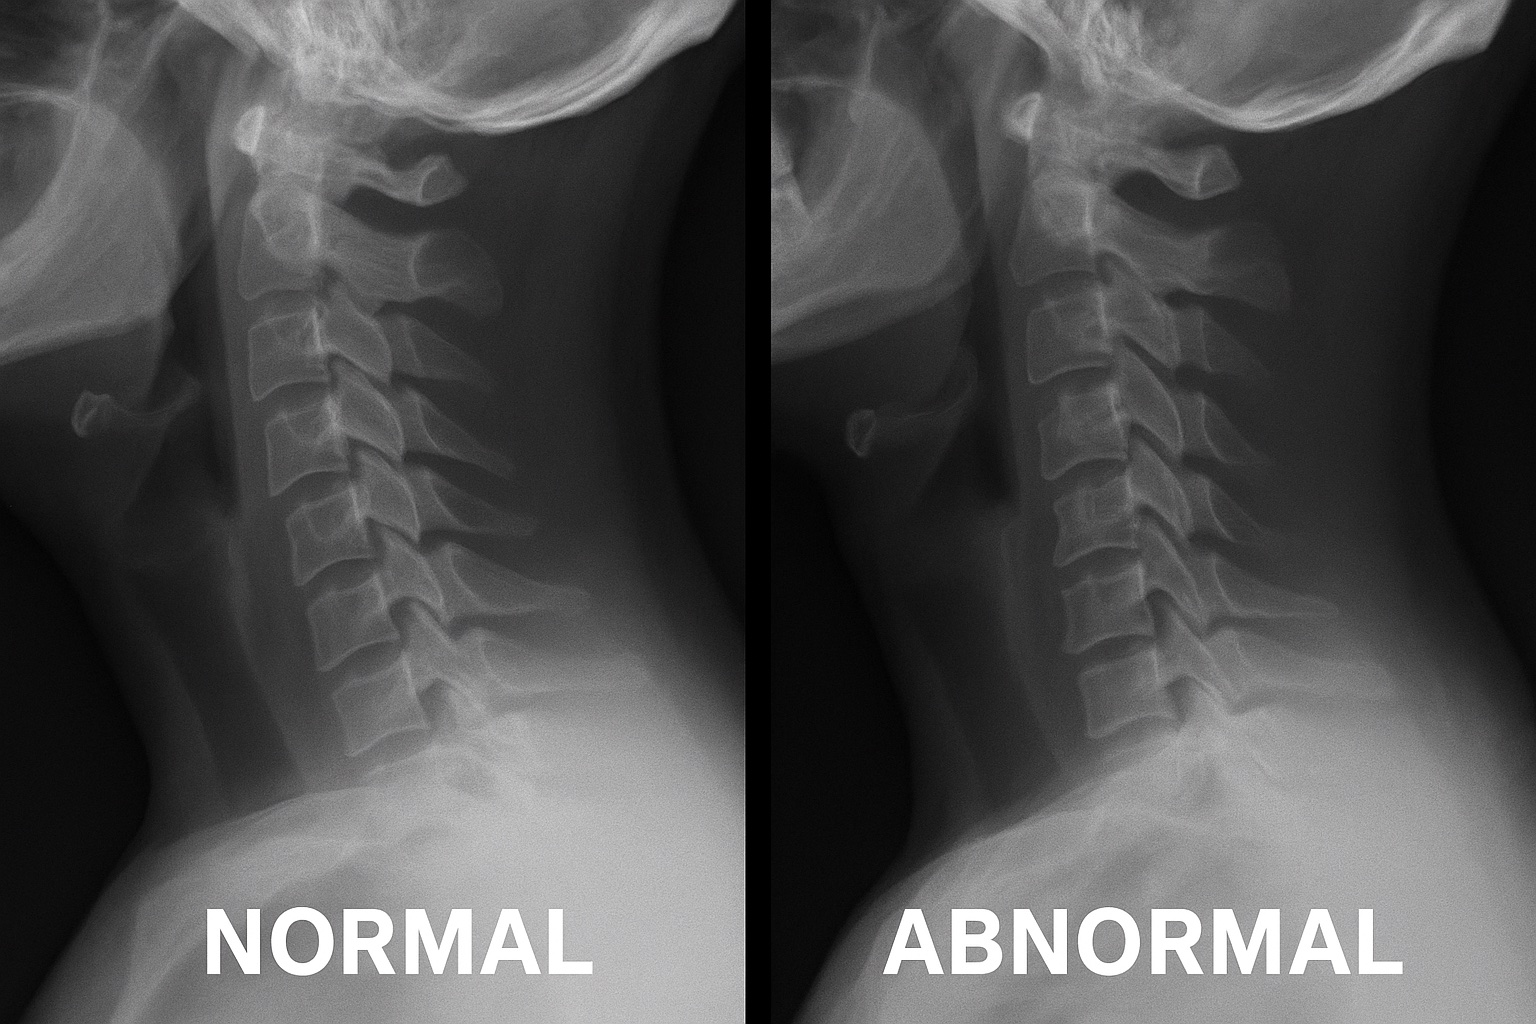

火曜のコラムでは、「骨棘そのものより、首の骨の角度(アライメント)と周囲の硬さが症状を左右する」という話をしました。